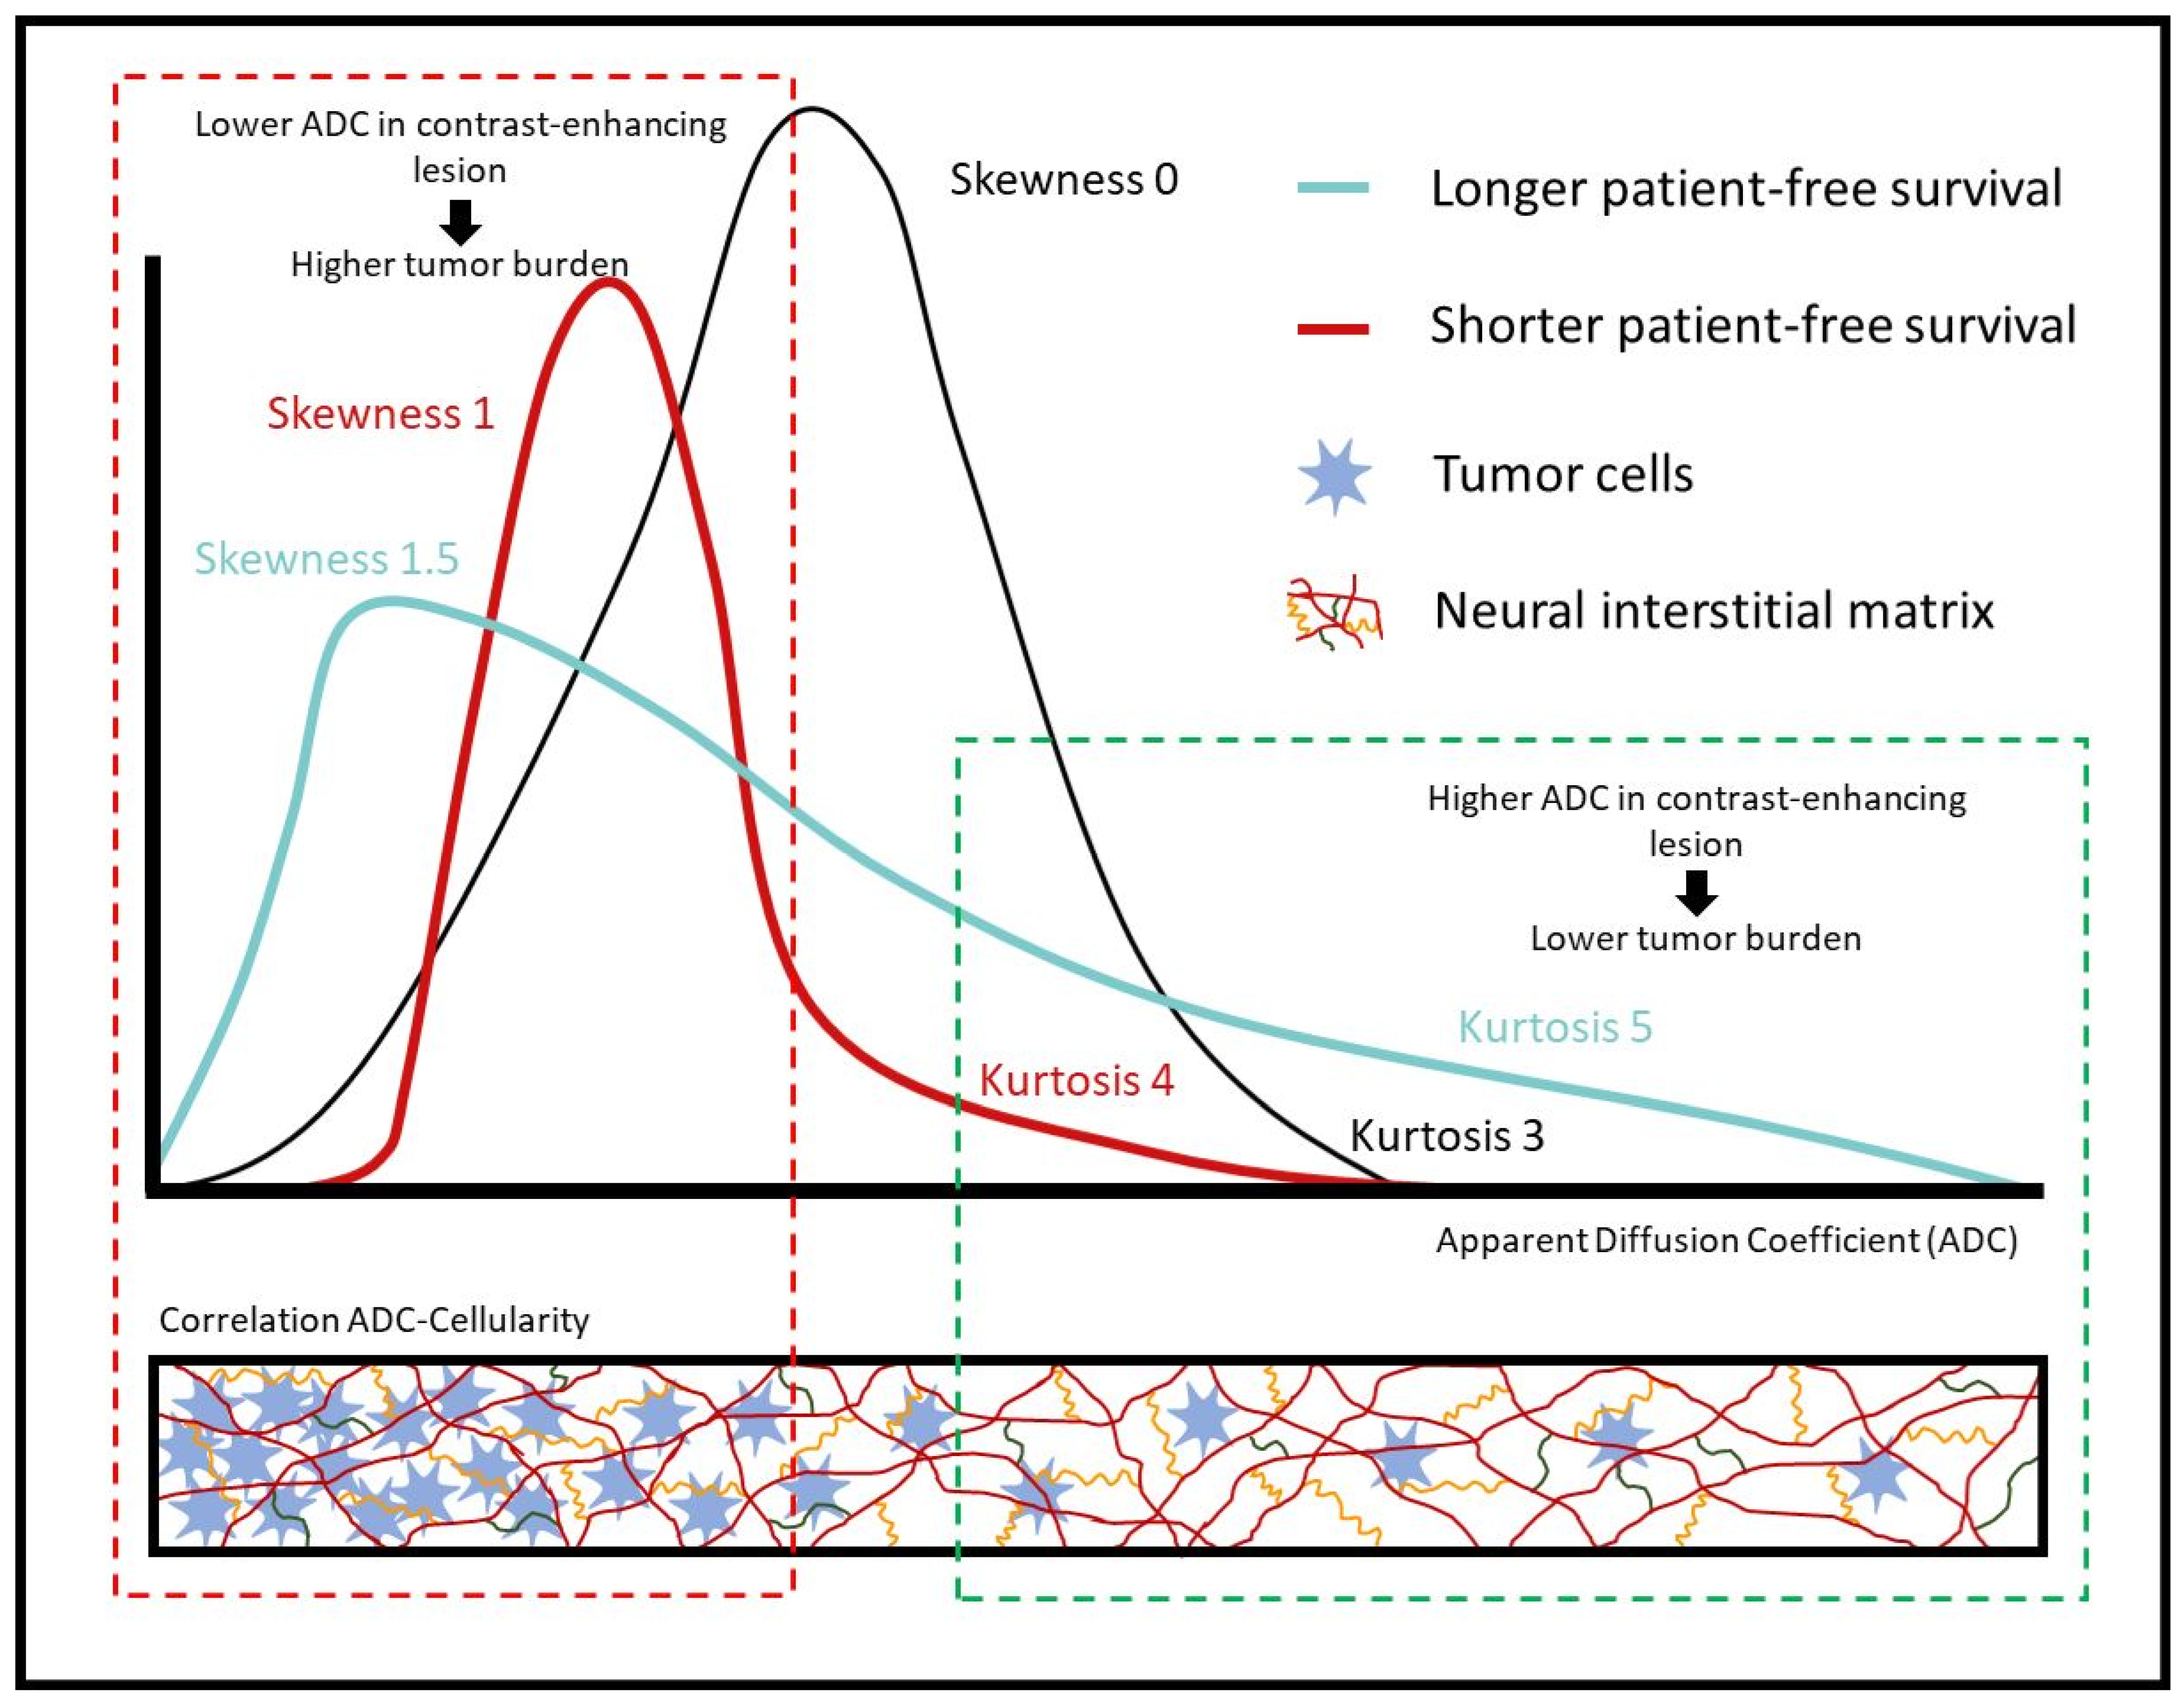

4. Discussion